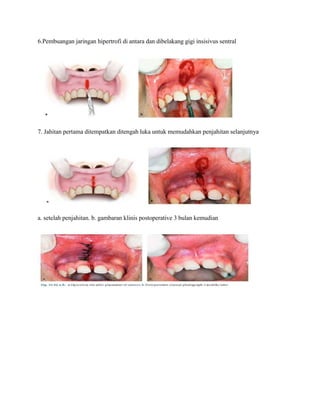

6.Pembuangan jaringan hipertrofi di antara dan dibelakang gigi insisivus sentral

7. Jahitan pertama ditempatkan ditengah luka untuk memudahkan penjahitan selanjutnya

a. setelah penjahitan. b. gambaran klinis postoperative 3 bulan kemudian